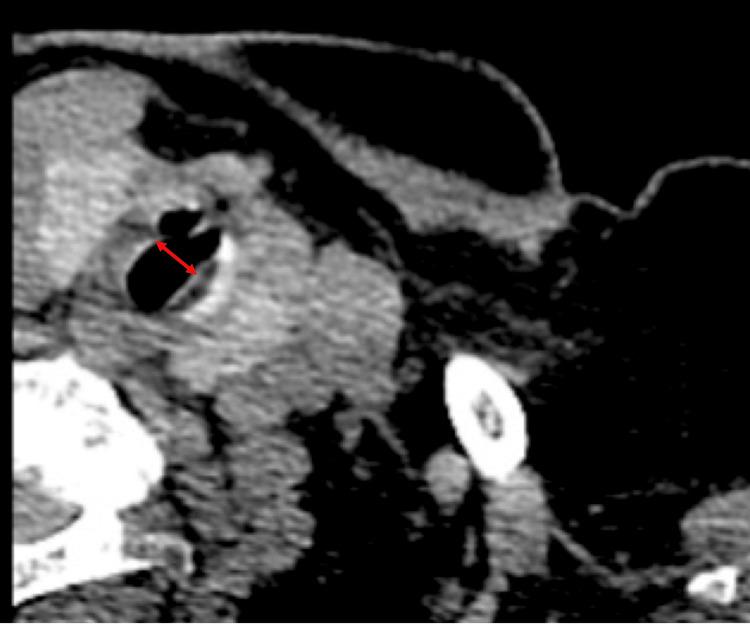

Subglottic stenosis (SGS) can be asymptomatic in cases with slow-growing granulomas. In this study, we report a case of SGS discovered during tracheal intubation for anesthesia induction. A 74-year-old woman was scheduled for surgery under general anesthesia for a left humeral fracture. Resistance was observed when the tracheal tube passed through the glottis, stopping the tube from advancing. We placed a laryngeal mask (LMA) to secure her airway and examined it using a bronchial fiber to detect circumferential stenosis of the subglottis due to granulation. The airway was secured using an LMA instead of intubation, and the patient was successfully managed under anesthesia. Asymptomatic SGS is difficult to detect preoperatively, and anesthesiologists may encounter unexpected intubation issues. LMA is an important tool for an effective strategy to manage intubation difficulties.

声门下狭窄(SGS)在肉芽肿生长缓慢的情况下可能无症状。在本研究中,我们报告了一例在麻醉诱导气管插管期间发现的SGS病例。一名74岁女性计划在全身麻醉下进行左肱骨骨折手术。当气管导管通过声门时观察到阻力,导致导管无法推进。我们放置了喉罩(LMA)以确保气道安全,并使用支气管纤维镜检查以检测由于肉芽组织导致的声门下环形狭窄。使用LMA而非插管确保了气道安全,患者在麻醉下成功完成手术。无症状性SGS术前难以检测,麻醉医生可能会遇到意外的插管问题。LMA是应对插管困难有效策略的重要工具。